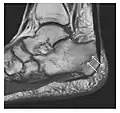

The greater tuberosity of the humerus is also an illustrative location of occult fractures. The osseous injury may follow seizures, glenohumeral dislocation, forced abduction, or direct impaction. They are commonly discovered on MRI in symptomatic patients with suspicion of rotator cuff tear. Coronal images are best suited for detection. They appear as crescentic oblique lines surrounded by a bone marrow edema pattern (Figure 5). The rotator cuff must be inspected since associated ligamentous lesions are common. In the ankle, malleoli and tarsal bones should be checked carefully for any cortical disruptions and radiolucent lines that may reveal a fracture. Awareness of the exact location of the pain will help direct the attention of the interpreter when searching for very subtle signs of fracture (Figure 6).[1]

a

b

Figure 6: Subtle anterior talar fracture in a 39-year-old man presenting with ankle pain after a fall. (a) Anteroposterior radiograph shows a subtle oblique radiolucent line through the talus (white arrows). (b) Sagittal CT reformation confirms the presence of an anterior talar fracture with cortical offset (black arrow). Avulsion fractures, which consist of a detached bone fragment resulting from a ligament or tendon pulling away from the bone, may also present with subtle radiographic signs. Tiny osseous fragments near the presumed attachment site of a ligament suggest this diagnosis. Common sites are the lateral tibial plateau (the Segond fracture), the spinal tuberosity of the tibia resulting from anterior cruciate ligament avulsion, and the ischial tuberosity.[1]